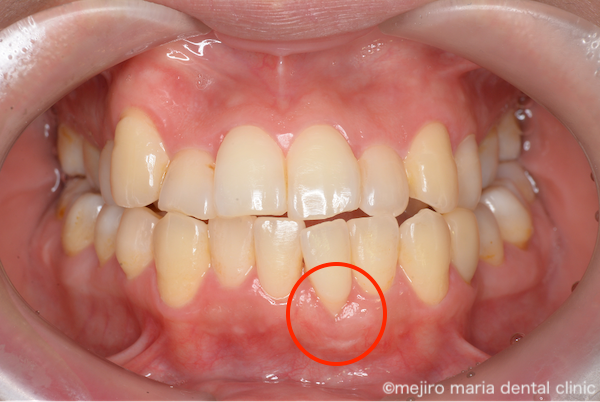

治療後の様子

術後経過3ヶ月後の状態です。術前に大きく歯茎下がりが確認できていた部位が改善しているのがわかります。患者様は術前にあった知覚過敏もなくなり、また審美的にも満足されています。今後は適切なブラッシングを継続していただくことで歯茎下りの再発を防いでいくことが必要です。